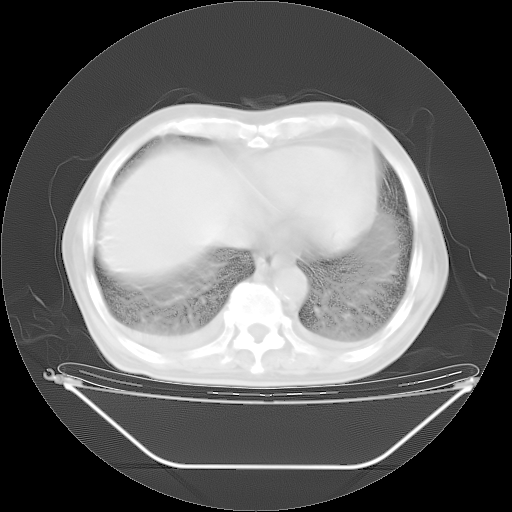

今天复查肺部CT,发现双肺广泛磨玻璃样改变。所以我把3月19日和5月9日相隔50天的肺部CT上传。请大家会诊。

2009年3月19日肺部CT片。

5月9日肺部CT(在4月27日齐鲁医院肺部CT描述部分肺组织磨玻璃样改变,12天后肺组织广泛磨玻璃样改变)